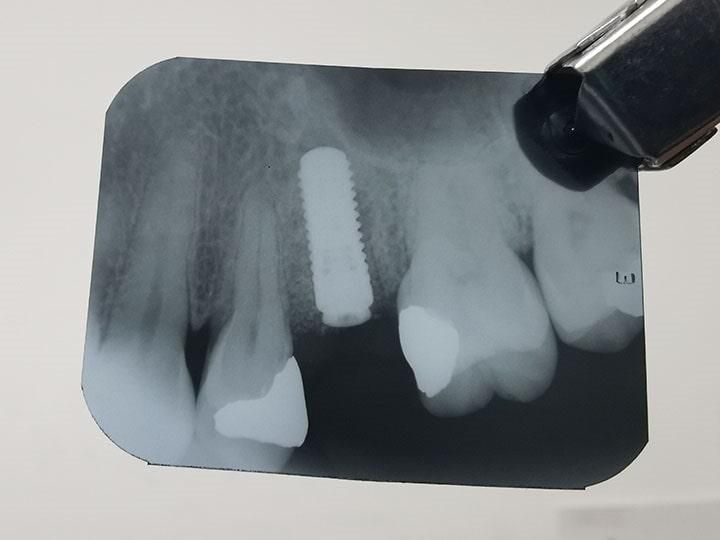

IMPLANTES

DENTALES

Antes de pensar en colocar un implante, primero deberemos realizarte una serie de estudios, así como valoración a detalle de tu cavidad oral para proponer que tratamiento es el ideal para ti.

En CIMOH contamos con equipo multidisciplinario para lograr evaluarte y decidir si eres o no candidato para este tipo de tratamientos, en caso de no serlo, también de sugeriremos diferentes opciones para tu rehabilitación.